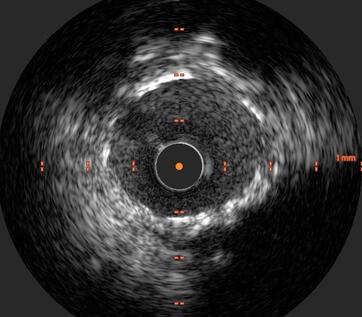

Der intravaskuläre Ultraschall (das heißt „innerhalb

des Blutgefäßes“) wird mithilfe eines

speziellen Ultraschallkatheters durchgeführt.

Der

Gefäßultraschall liefert dem Arzt wichtige Zusatzinformationen zur Behandlung von

Erkrankung wie beispielsweise einer Dissektion (Einrisses) der Gefäßinnenwand.

Unter den heute verfügbaren Untersuchungsmethoden ist der Gefäßultraschall die

Methode mit der höchsten Genauigkeit.

Die Gefäßultraschalluntersuchung wird im Rahmen einer Linksherzkatheteruntersuchung durchgeführt. Ein dünner Draht wird in die Herzkranzarterie eingelegt. Dieser Draht dient, ähnlich wie bei der Ballonaufdehnung als Leitschiene für den Ultraschallkatheter. Ein dünner Kunststoffkatheter mit einem Durchmesser von ca. 1mm, an dessen Ende sich eine sehr kleine Ultraschallsonde befindet. Diese wird in die Herzkranzarterie eingeführt.

Die Ultraschallsonde liefert Bilder aus dem Inneren der Herzkranzarterie und zeigt alle Wandschichten der Arterie in einem Querschnittsbild. Die Auflösung der Ultraschallsonde ist sehr hoch, kann damit neben kleinsten Ablagerungen auch den genauen Ort eines Einrisses in der Gefäßwand zeigen und erlaubt damit eine passgenaue Therapie mittels Stentimplantation.